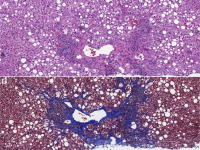

王功伟老师肾脏肿瘤系列讲座(二十九)一个好汉三个帮:嫌色细胞肾细胞癌病理诊断基础